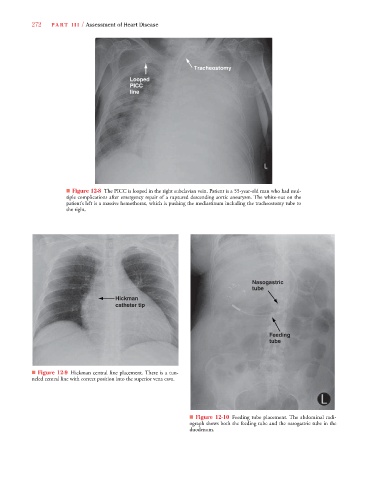

■ Figure 12-8 The PICC is looped in the right subclavian vein. Patient is a 55-year-old man who had mul-

tiple complications after emergency repair of a ruptured descending aortic aneurysm. The white-out on the

patient’s left is a massive hemothorax, which is pushing the mediastinum including the tracheostomy tube to

the right.

■ Figure 12-9 Hickman central line placement. There is a tun-

neled central line with correct position into the superior vena cava.

■ Figure 12-10 Feeding tube placement. The abdominal radi-

ograph shows both the feeding tube and the nasogastric tube in the

duodenum.